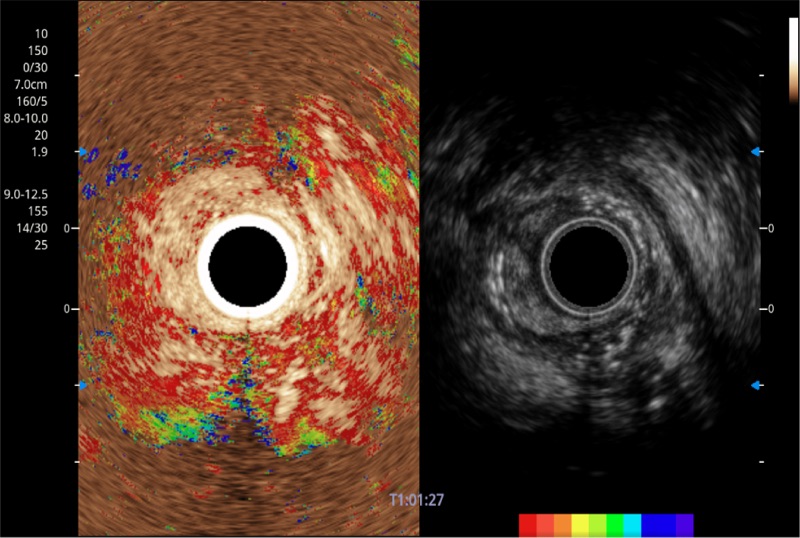

可人为将灰阶图像转变成彩色的显示方式,增强人眼对于不同回声强度的敏感度,主观上增加了图像分辨率

微米成像技术提升了对组织斑点噪声信号的抑制能力,并进一步强化边界信息,从而获得信噪比更优、边界更清楚锐利的图像

随着组织深度的变化,超声接收频率进行智能匹配跟踪,确保图像中、远场良好的穿透力以及整场一致的分辨力,从而得到均一的画质

具有四种造影成像效果